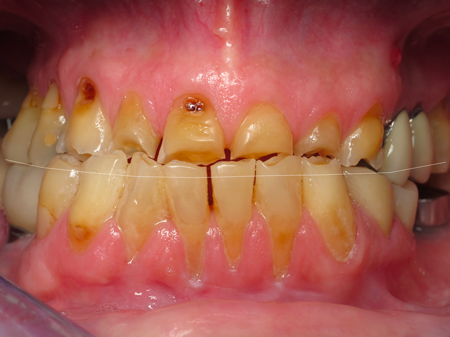

3. In a single arch case, reducing the opposing dentition is a quick way to gain a millimeter or two. We usually see this with super-erupted lower anterior teeth, especially if there is crowding. Performing an enamelplasty to equilibrate the opposing arch is a quick and easy opportunity to gain space.

4. Another opportunity in a single arch case – and when treatment time is on your side – is to consider orthodontic intrusion of the opposition dentition. We recently completed a maxillary arch, and the patient was extremely happy with the results. The lower dentitions were in great shape despite being crowded anteriorly with an uneven plane from canine to canine. She was excited to initiate orthodontics as an option to level and align her mandibular arch, and we were able to intrude the incisors 1.5 mm. This can be accomplished during the healing period when in the provisional.